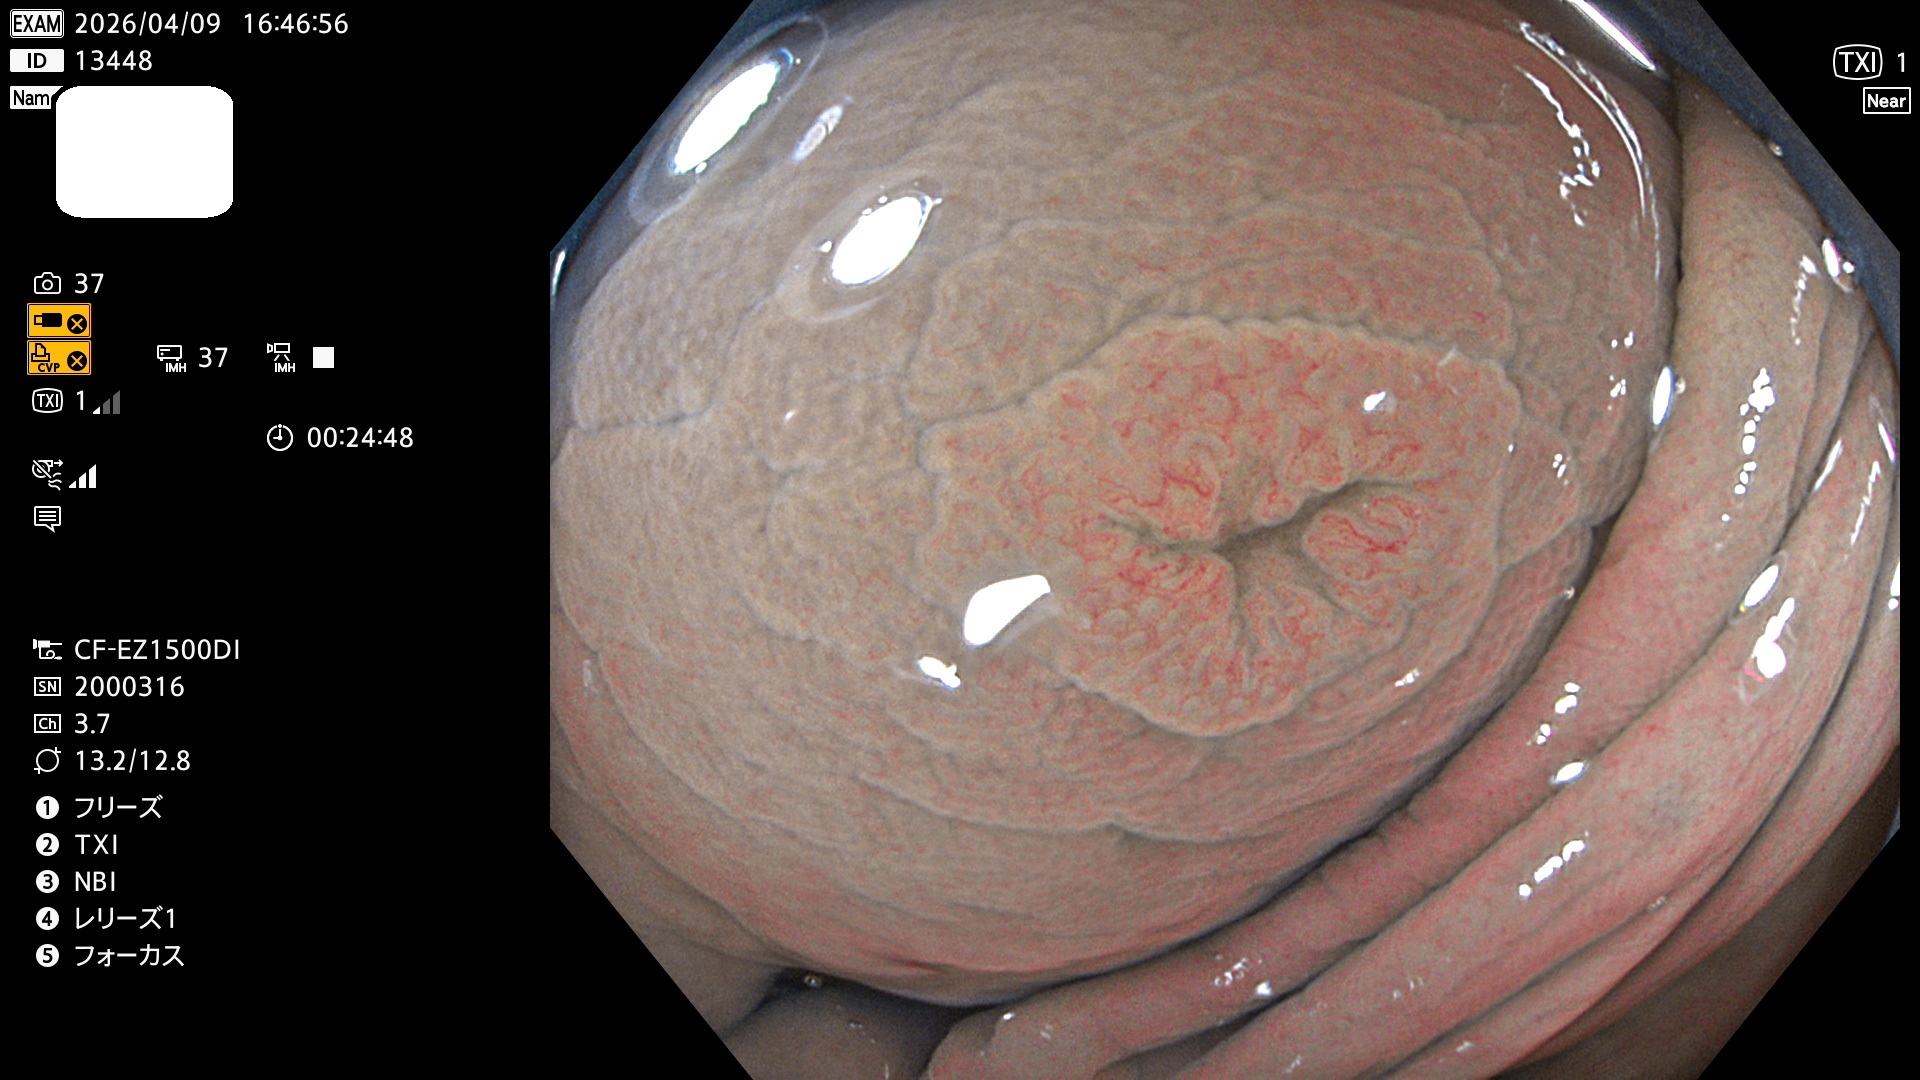

完全に平坦な物をUb、陥凹している物をUcと呼びます。Ubは認識が困難で、Ucはびらん(炎症)と紛らわしいために見落とされやすく、「内視鏡後・大腸癌」の原因になります。

専門的)Uc=De Novo癌? 内視鏡の解像度が低かった時代、このような説もありました。しかし今日の高精度内視鏡では良性の微小なUc型腺腫(APC遺伝子異常の腺腫)が日常的に見つかります。Ucこそが多段階発癌(Adenoma-Carcinoma Sequence)のMain Routeです。

毎週の検査(木・金・土・日)に発見されたUbとUc型・腺腫を、その週の日曜の夜にUPし1週間、提示します。

写真公開の目的は「透明性・信憑性の担保」ですが、公開を希望されない方はメールで御連絡下さい。直ちに削除いたします。

2026年4月9日〜4月12日の4日間(40件)で6個 (Uc_ADR=6個/40人=15%)